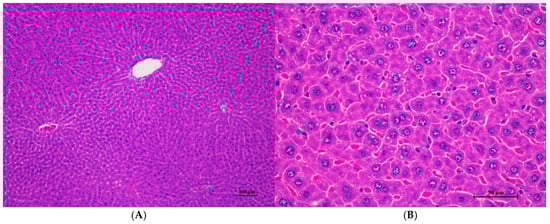

Figure 1.

Histopathological examination of rat liver tissue in acute toxicity from a single oral dose of CDF demonstrated minimal and non-pathological changes. (A) The hepatic parenchyma showed a normal central vein, hepatic portal triad, and hepatic cord (100×, H&E). (B) High magnification shows polygonal hepatocytes with central nuclei. Very mild cytoplasmic swelling and fine vacuolation were observed in some hepatocytes (400×, H&E).

The male rats were orally given a single dose of CDF at doses of 175 (175AM), 550 (550AM), and 2000 (2000AM) mg/10 mL/kg, and female rats were given CDF at doses of 175 (175AF), 550 (550AF), and 2000 (2000AF) mg/10 mL/kg, respectively. There were no significant signs of mortality, general behavior, or gross differences in appearance in the internal organs during the 14 days of the testing period. However, there were increases in body weight gain in both the control and the treated groups. A gross and histopathological examination of the liver showed that the internal organs did not reveal any pathological abnormality relative to the control (Table 1, Table 2, Table 3, Table 4, Table 5, Table 6, Table 7, Table 8 and Table 9). It was further confirmed that the CDF did not cause any tissue damage (Figure 1, Figure 2, Figure 3, Figure 4 and Figure 5).

Histopathological analysis revealed generally unremarkable findings in the liver, kidney, heart, and spleen, with only minor, scattered hepatocellular swelling and vacuolation in the liver, mild renal tubular degeneration in limited kidney areas, and focal myocardial vacuolation and lymphoid aggregation in the heart. Conversely, the lung exhibited significant pathological changes, characterized by alveolar septal thickening due to severe interstitial infiltration of lymphocytes and other mononuclear cells, nodular lymphoid aggregations, alveolar septal engorgement and hyperemia, alveolar edema, and multifocal mild alveolar hemorrhage, suggesting a potential site of inflammatory response.